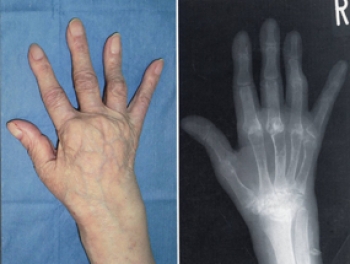

関節リウマチは、膠原病の一つで、炎症性自己免疫疾患です。

主に手足の関節を侵し、これにより関節痛、関節の変形もしくは破壊が現れます。

また、関節の滑膜が炎症をおこす病気です。

関節の変形や滑膜の細胞が増殖したり、軟骨の破壊が始まる。その後、関節も破壊し、関節は動かなくなってしまいます。

手の指の関節、第2関節(PIP)、第3関節(MP)が特に侵されます。また、手首や足の指、肘、膝など体の中心に近い大きな関節の痛みが出てくることもあります。

指の変形がひどくなると

スワンネック変形(白鳥の首状の変形)

ボタン穴変形

尺側偏位(指の全てが外側を向く変形   になります

レントゲン検査で典型的な関節所見

レントゲン